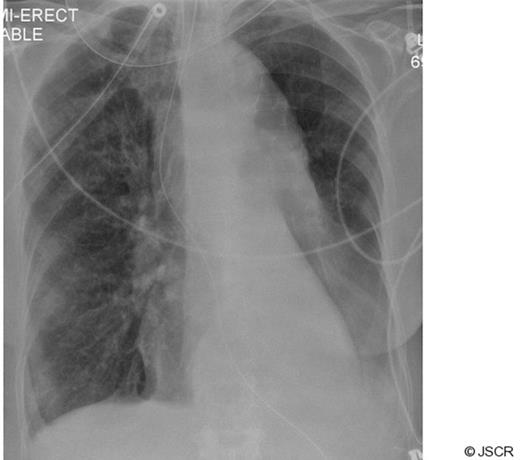

A 77 year old lady presented after an episode of chest pain and dyspnoea. Clinical examination was unremarkable apart from a low grade temperature of 37.8 oC and breath sounds were equal bilaterally. There was no evidence of cardiac ischaemia on an electrocardiogram. Inflammatory markers (white cell count and C-reactive protein) were raised. The cardiac enzyme levels were within normal limits. Empirical antibiotic therapy was instituted for a clinical diagnosis of lower respiratory tract infection. After admission the patient's condition deteriorated with increasing dyspnoea and a worsening PaO2 / FiO2 ratio. Her chest radiograph showed a complete “white-out” of her left lung field (Fig 1). Her trachea was intubated and her lungs mechanically ventilated.